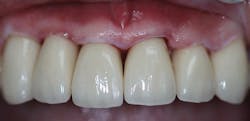

Upon his return three weeks later, the provisional was removed and the definitive laboratory-fabricated crowns were tried-in (figure 7). With excellent margins, this impression material speaks to the accuracy of capturing preparation detail, eliminating this potential concern and allowing the practitioner peace of mind.

Figure 7: Final crown try-in